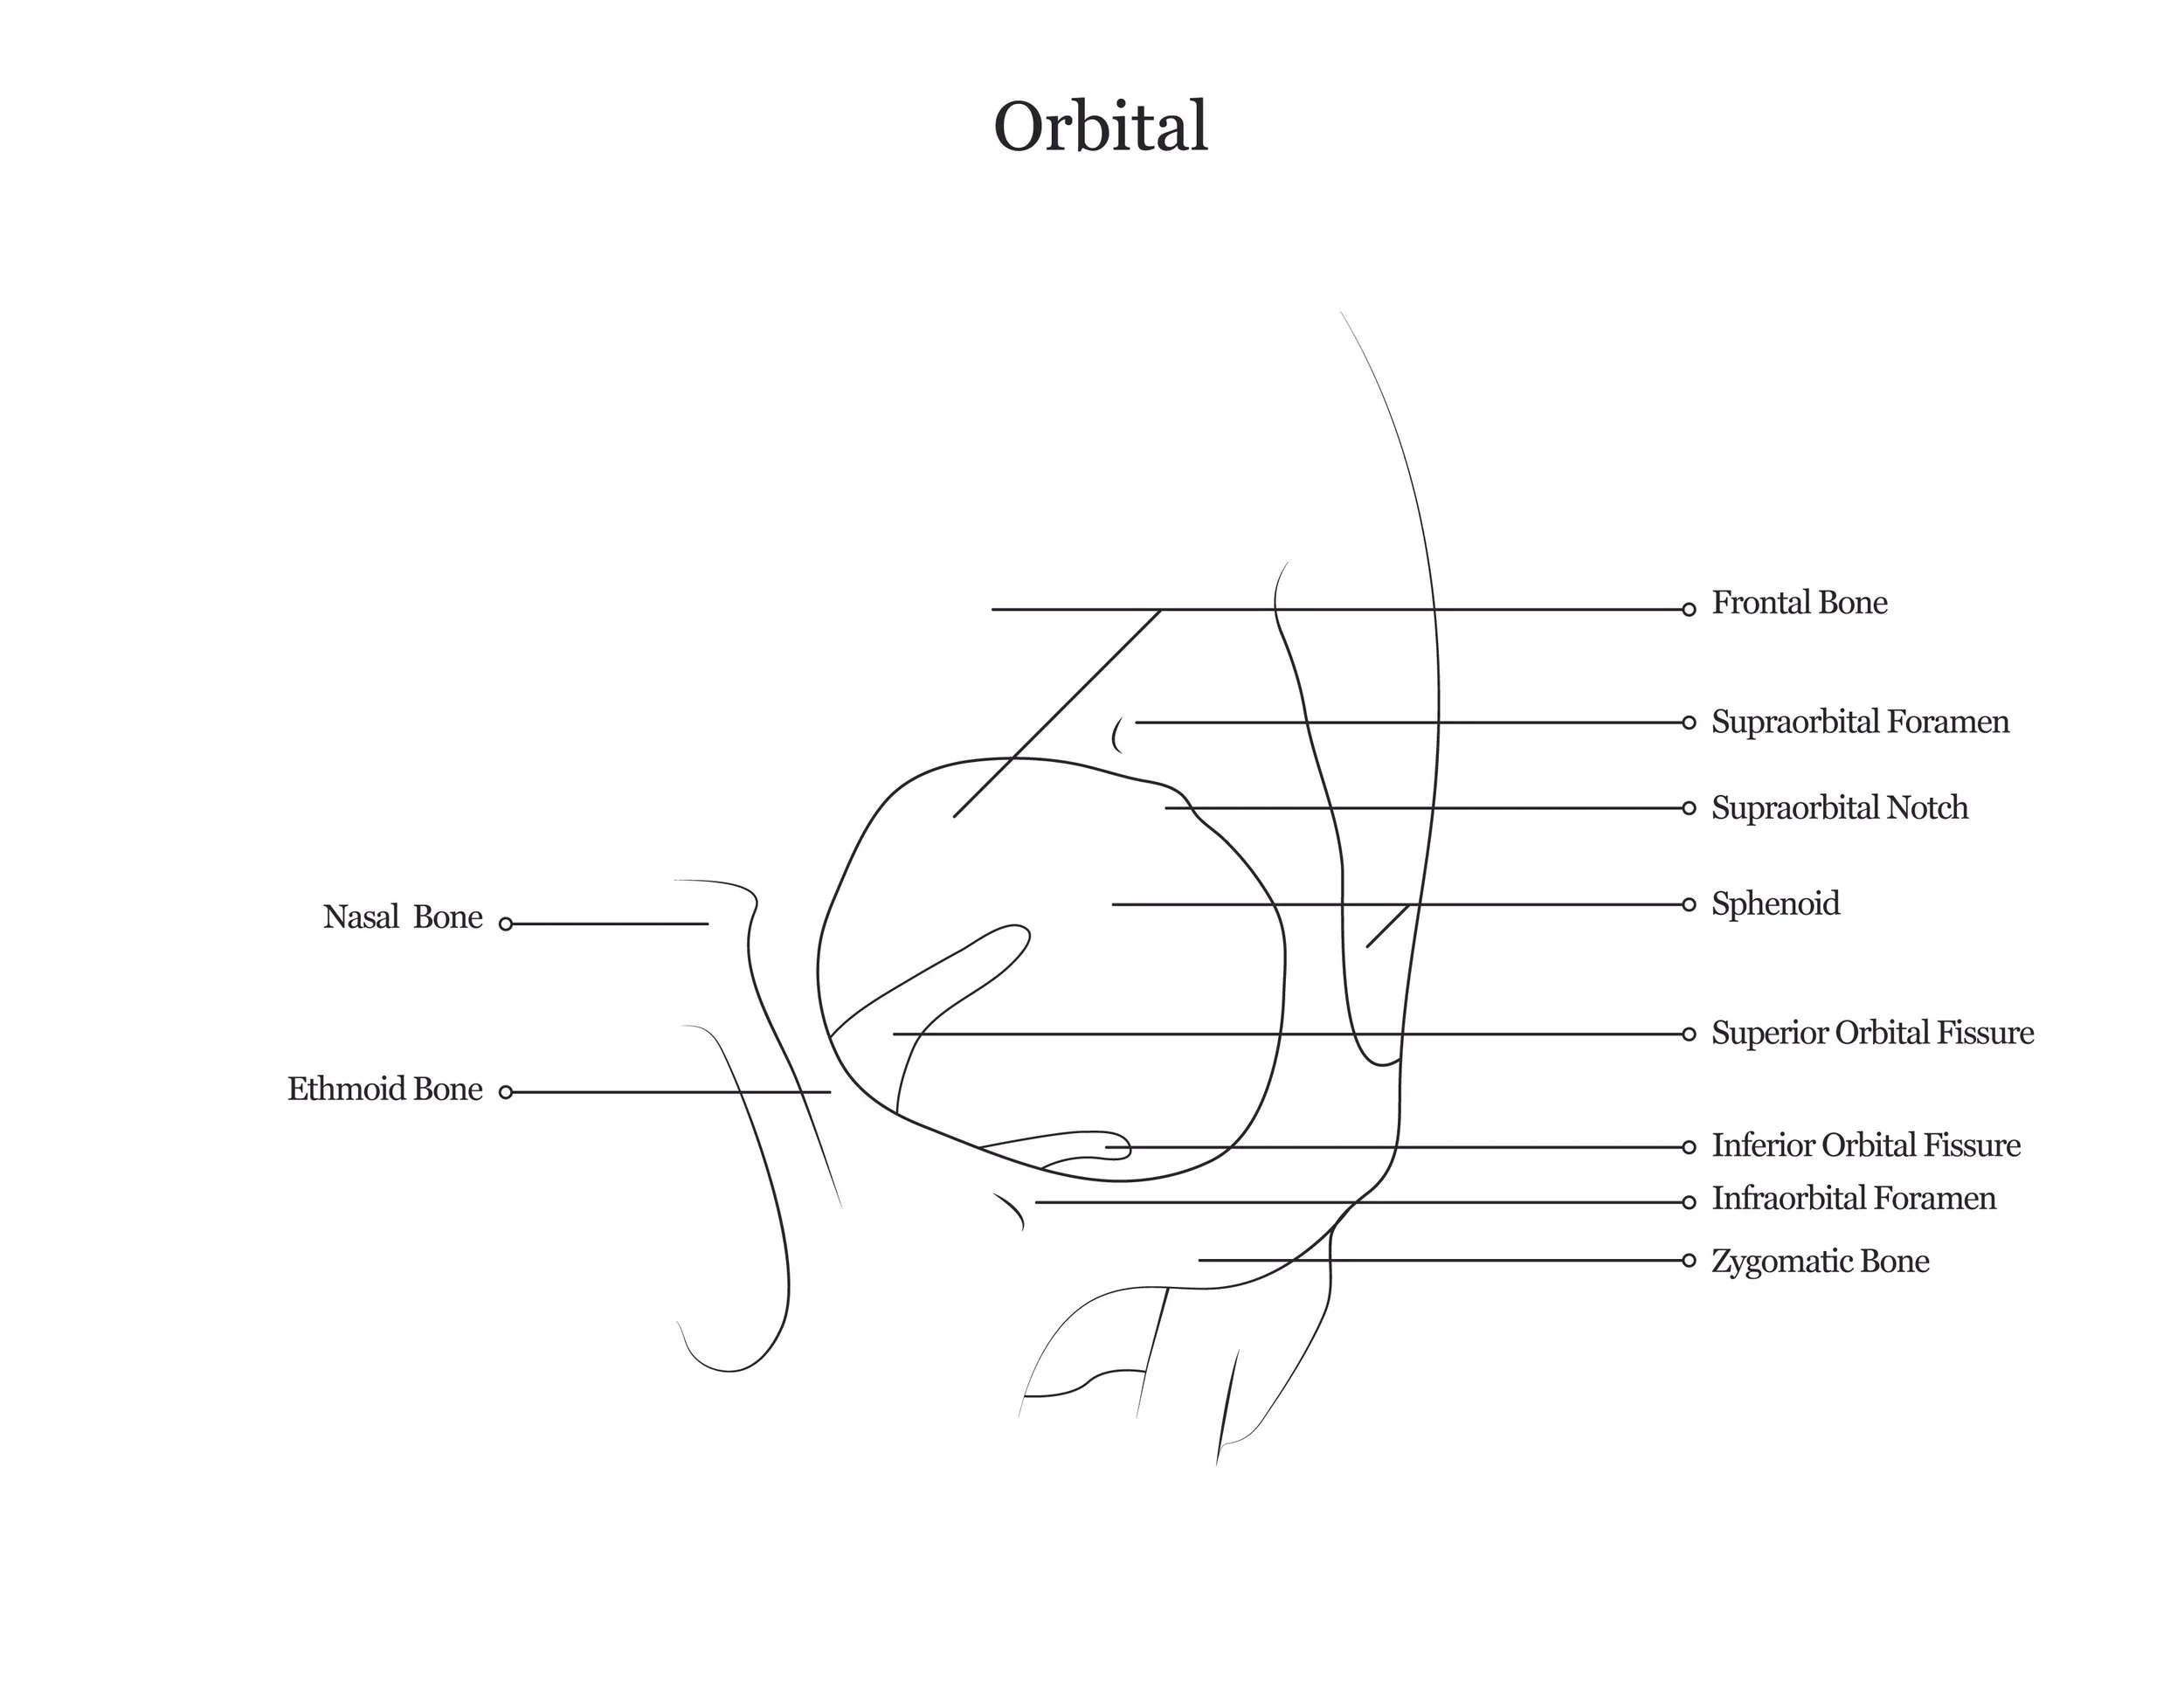

A series of anatomical illustrations created for Arcadia University’s Biology Department.

This project involved illustrating a series of diagrams for a cat dissection manual, focusing on skeletal and muscular anatomy. I consolidated multiple reference sources and firsthand specimen observation into a cohesive visual system for instructional use. Illustrations were refined iteratively to ensure anatomical accuracy, consistency, and clarity for students.